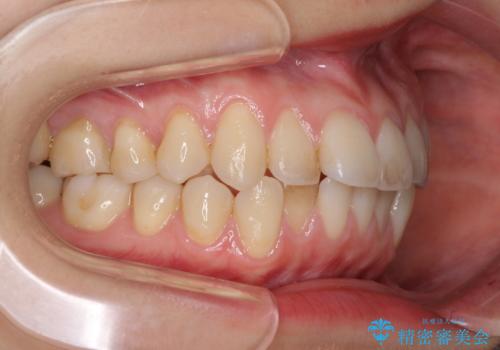

- 上下前歯のデコボコを気にして来院された患者様です。

インビザラインによる上下歯列の側方拡大と後方移動、IPR(歯と歯の間を削る)にるスペースの獲得により歯列を整えることとしました。